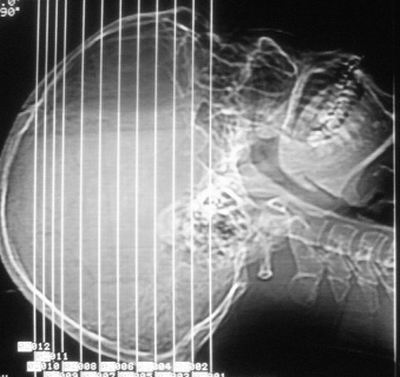

建议:必要时行进一步检查排除烟雾病。

支持,建议进一步检查排除血管畸形(动脉瘤 等)

建议mr查明出血原因。